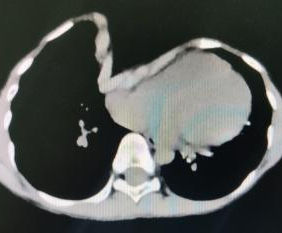

A severe depression is present in the center of the chest wall, with the right edge of the depression forming a ridge-like protrusion. Meanwhile, the edges and bottom of the depression have developed acute angle deformities.

We began by pre-shaping the depression to effectively release local stress and simplify the complex deformities. The Wung procedure and the Wang procedure were then simultaneously performed to correct the severe pectus excavatum and associated acute angle deformity. After the surgery, the chest wall deformity was completely resolved, and its appearance returned to normal.

Acute angle deformity refers to a specific type of localized deformity where a sharp angle forms in areas of significant protrusion or depression of the chest wall. This malformation does not exist independently but rather manifests as a feature within a diverse range of chest wall deformities, encompassing single deformity such as pectus excavatum and pectus carinatum, as well as various complex deformities.